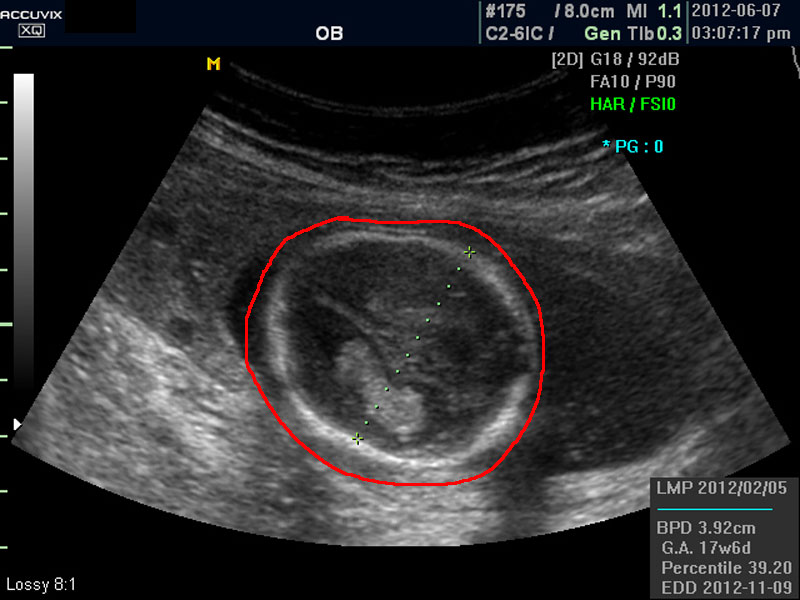

태아의 머리가 정상 모양인가 크기는 정상인가 하는 것을 살펴 본 후에는 태아의 크기를 측정하고 가슴, 복부, 엉덩이 부분, 상하지 부분이 정상인가 하는 것을 살펴 봅니다.

위 사진에서 빨간 동그라미로 표시한 부분이 태아의 머리를 위에서 내려다 본 수평 단면입니다.

하얗게 보이는 것은 뼈이고 내부에 검게 보이는 것은 뇌실에 고인 척수액 부분이며 내부의 하얀 부분은 뇌조직과 뇌실 내 맥락막이라고 하는 것입니다.

모든 사진에서 우측 하단에는 기본적인 발육 정보가 기록되는데 세번째 사진에서 빨간 펜으로 표시한 부분이며 그 내용의 의미는 아래와 같습니다.

참고로 이런 측정 수치가 나타나는 양식이나 위치는 초음파 장비마다 다르지만 용어는 대체로 공통된 의학 용어를 사용하기 때문에 대동소이합니다.

4. BPD

Biparietal Diameter의 약자로 머리를 위에서 보아서 양쪽 옆통수에서 반대쪽 옆통수까지의 길이입니다.

이는 임신 중기부터 후기까지 태아의 발육을 판단하는 중요한 지표이며 태아의 체중을 예측하는 데 쓰이는 지표 중 하나입니다.

5.EDD

Estimated Due Date의 약자로 초음파 측정치를 바탕으로 산출한 출산 예정일입니다.